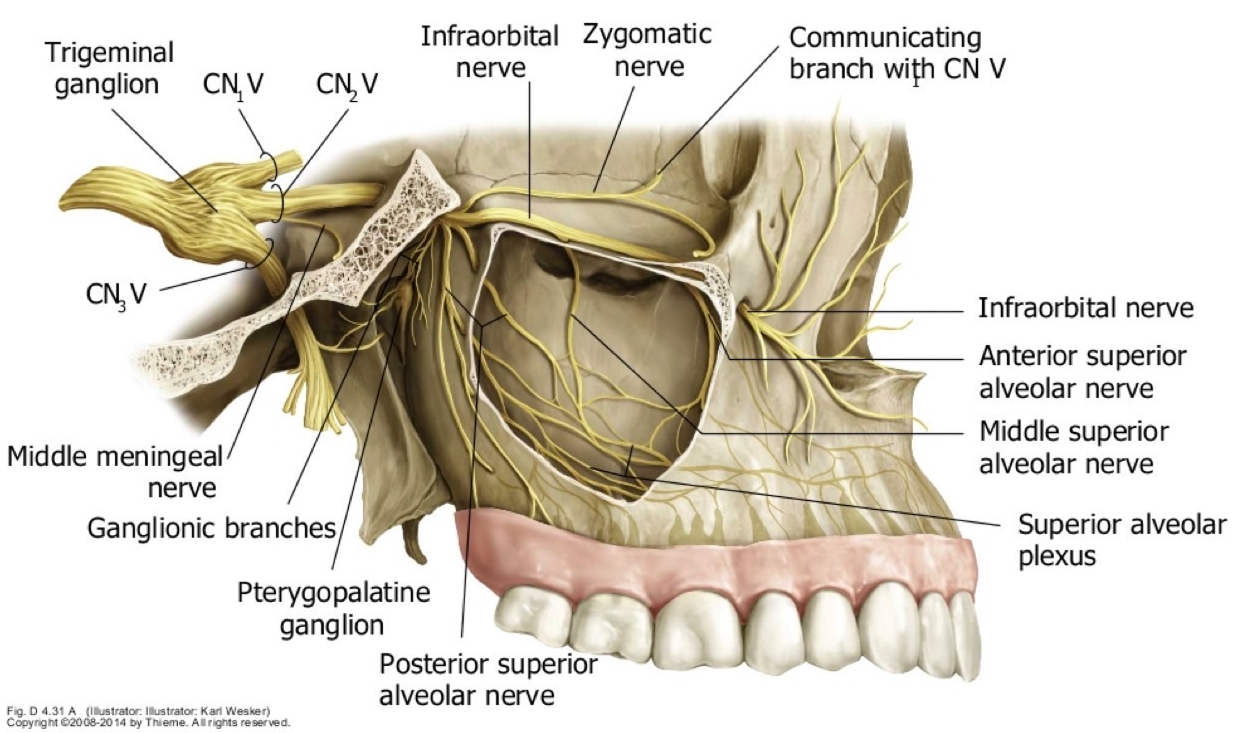

CN V2

Post. sup. alveolar n.

穿過 pterygomaxillary fissure,支配上顎臼齒(molars),除了第一大臼齒(mid. sup alveolar n.)

Infraorbital n.

感覺神經

- Ant./Mid sup. alveolar n.

- 與動脈伴行

- Sup. labial br.

- Nasal br.

Pterygopalatine ganglion